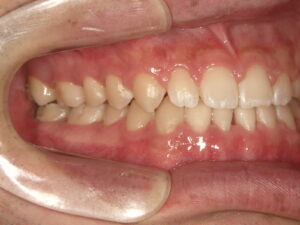

②外科手術後

外科手術後の状態です。下顎の位置は下がり、受け口が改善されましたが、上下のかみ合わせのズレがあります。